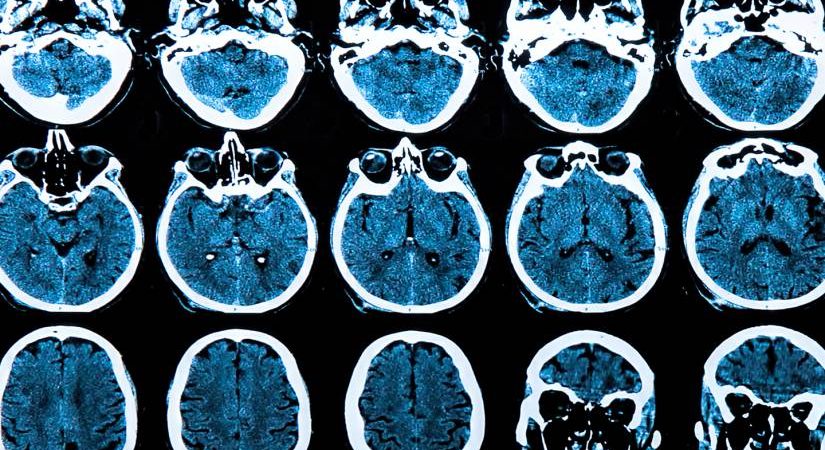

Një studim i fundit i cili ka krahasuar skanerit e trurit të shumë pacientëve para dhe pasi infektohen me Covid-19, ka zbuluar tkurrje të trurit dhe dëmtim të indeve në rajonet e lidhura me nuhatjen dhe aftësitë mendore.

Studiuesit në Universitetin e Oksfordit studiuan 785 njerëz të moshës midis 51 dhe 81 vjeç. Krahasuar me 384 persona të pa infektuar, ata që rezultuan pozitivë për Covid-19, ishin më të prekur nga tkurrja e trurit dhe veçanërisht në zonat e lidhura me nuhatjen. Për shembull, ata që kishin Covid-19 kishin tkurrje prej 1.8% të gyrusit parahipokampal, një rajon kyç për nuhatjen dhe një tkurrje 0.8% të trurit të vogël, në krahasim me pjesën tjetër që e kishin kaluar virusin.

Efektet ishin më të theksuara te njerëzit e moshuar dhe ata të shtruar në spital nga sëmundja, por ende të dukshme tek të tjerët, infeksionet e të cilëve ishin të lehta ose asimptomatike, tregoi hulumtimi, i cili u botua në revistën “Nature”.